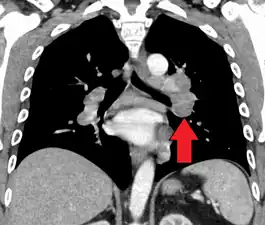

CT scan of the chest showing lymphadenopathy (arrows) in the mediastinum due to sarcoidosis

Diagnosis of sarcoidosis is a matter of exclusion, as there is no specific test for the condition. To exclude sarcoidosis in a case presenting with pulmonary symptoms might involve a chest radiograph, CT scan of chest, PET scan, CT-guided biopsy, mediastinoscopy, open lung biopsy, bronchoscopy with biopsy, endobronchial ultrasound, and endoscopic ultrasound with fine-needle aspiration of mediastinal lymph nodes (EBUS FNA). Tissue from biopsy of lymph nodes is subjected to both flow cytometry to rule out cancer and special stains (acid fast bacilli stain and Gömöri methenamine silver stain) to rule out microorganisms and fungi.[100][101][12][102]

Chest radiograph changes are divided into four stages:[105]

1. bihilar lymphadenopathy

2. bihilar lymphadenopathy and reticulonodular infiltrates

3. bilateral pulmonary infiltrates

4. fibrocystic sarcoidosis typically with upward hilar retraction, cystic and bullous changes